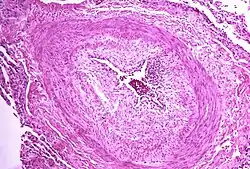

The pathogenesis of pulmonary arterial hypertension (WHO Group I) involves the narrowing of blood vessels connected to and within the lungs. This makes it harder for the heart to pump blood through the lungs, as it is much harder to make water flow through a narrow pipe as opposed to a wide one. Over time, the affected blood vessels become stiffer and thicker, in a process known as fibrosis. The mechanisms involved in this narrowing process include vasoconstriction, thrombosis, and vascular remodeling (excessive cellular proliferation, fibrosis, and reduced apoptosis/programmed cell death in the vessel walls, caused by inflammation, disordered metabolism and dysregulation of certain growth factors).[27][28] This further increases the blood pressure within the lungs and impairs their blood flow. In common with other types of pulmonary hypertension, these changes result in an increased workload for the right side of the heart.[16][29] The right ventricle is normally part of a low pressure system, with systolic ventricular pressures that are lower than those that the left ventricle normally encounters. As such, the right ventricle cannot cope as well with higher pressures, and although right ventricular adaptations (hypertrophy and increased contractility of the heart muscle) initially help to preserve stroke volume, ultimately these compensatory mechanisms are insufficient; the right ventricular muscle cannot get enough oxygen to meet its needs and right heart failure follows.[16][28][29] As the blood flowing through the lungs decreases, the left side of the heart receives less blood. This blood may also carry less oxygen than normal. Therefore, it becomes harder and harder for the left side of the heart to supply sufficient oxygen to the rest of the body, especially during physical activity.[30][31][11] During the end-systolic volume phase of the cardiac cycle, the Gaussian curvature and the mean curvature of the right ventricular endocardial wall of PH patients were found to be significantly different as compared to controls.[32]

The cause is often unknown.[4] Risk factors include a family history, prior pulmonary embolism (blood clots in the lungs), HIV/AIDS, sickle cell disease, cocaine use, chronic obstructive pulmonary disease, sleep apnea, living at high altitudes, and problems with the mitral valve.[5][3] The underlying mechanism typically involves inflammation and subsequent remodeling of the arteries in the lungs.[5] Diagnosis involves first ruling out other potential causes.[4] High cardiac output states, such as advanced liver disease or the presence of large arteriovenous fistulas, may lead to an elevated mean pulmonary artery pressure (mPAP) greater than 20 mm Hg despite a pulmonary vascular resistance (PVR) less than 2 Wood units, which does not necessarily indicate pulmonary vascular disease.[9]